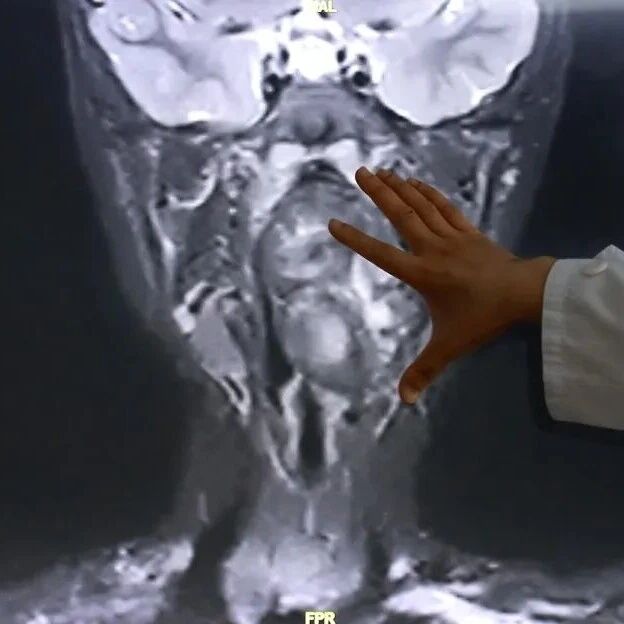

喉咙里竟然有“双胞胎兄弟”?!6岁男孩鼾声如雷,饮食习惯也古怪,一查是肿瘤。